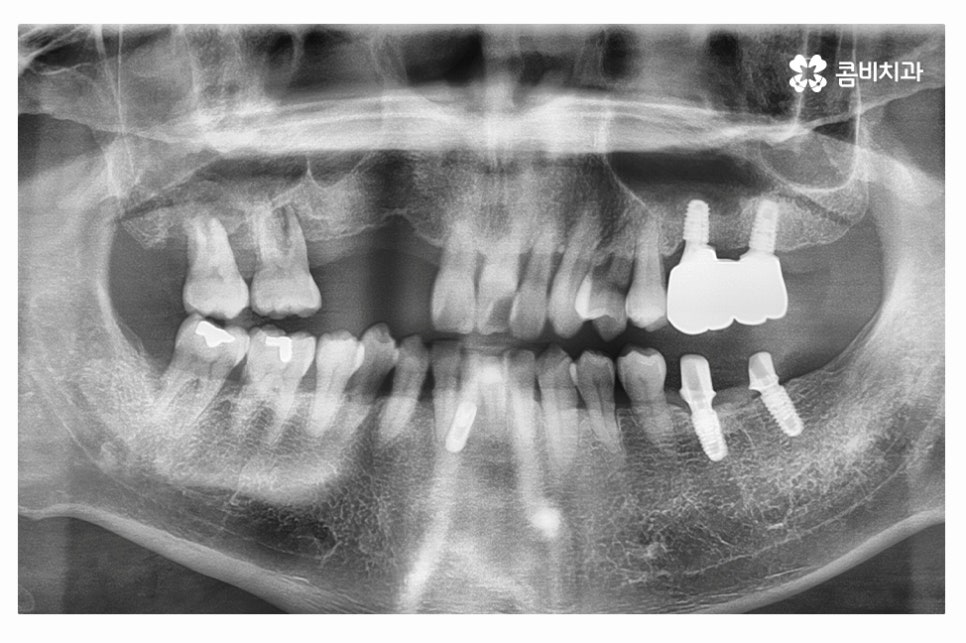

치주질환으로 인해 치아의 상당수를 한꺼번에 잃게 되면

임플란트의 저작력이 분산되는 것이 임플란트 수명 유지나

저작력의 부담을 줄이기에 유리하기 때문에

현재 구강 상태에 맞춰 1:1 맞춤 치료 계획을 세울 필요가 있어요.

임플란트를 위 사례처럼 여러 개를 식립할 경우에는

크라운을 여러 개를 이어 붙이게 되며 보통은 3~4개 정도 연결할 수 있고

4개가 넘어갈 경우에는 나눠서 연결하고 크라운을 씌우는 과정을 거칠 수 있어요.